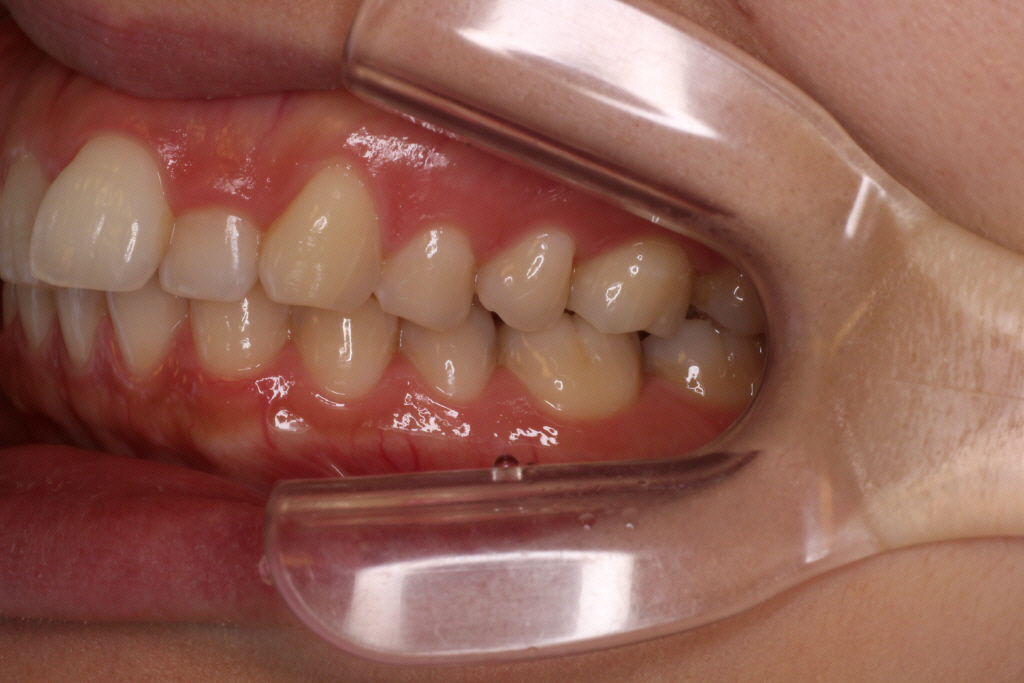

こちらがカリエールモーション終了時の口腔内写真です。

正中のずれが治ってきているのと、

上の前歯のがたつきが少しよくなっているのが分かります。

また、右の奥歯が1歯分後ろにさがっている事が分かります。